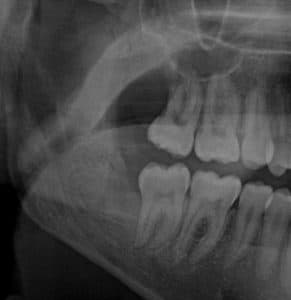

Vengono effettuate estrazioni di denti inclusi il cui studio pre-operatorio è affidato ad una attenta valutazione radiografica pre-operatoria tramite ortopantomografia o Tac.

L’estrazione dei terzi molari o denti del giudizio è uno degli atti più frequenti che si eseguono in chirurgia orale.

I terzi molari sono gli elementi permanenti più posteriori nelle arcate dentali e sono anche gli elementi che si formano ed erompono più tardivamente (tra i 17 e 25 anni) e sono spesso colpiti da disturbi malformativi o di posizione.

Succede molto spesso che i denti del giudizio non abbiano spazio a sufficienza per poter erompere in arcata e che rimangano inclusi nell’osso. In alternativa può capitare che questi elementi erompano, parzialmente o interamente, ma con una posizione non corretta.

I denti inclusi possono causare dolore, andando incontro ad infezione, e determinare danni ai denti e/o alle strutture adiacenti o addirittura dare origine a cisti della mandibola.

Nessuno può prevedere quando un dente incluso determina complicanze, ma il loro manifestarsi può essere molto più doloroso e con l’aumentare dell’età e quindi più complessa potrà essere la terapia chirurgica.